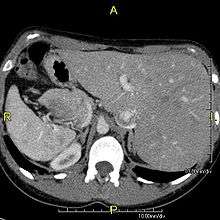

When accompanied by the combination of situs inversus (reversal of the internal organs), chronic sinusitis, and bronchiectasis, it is known as Kartagener syndrome (only 50% of primary ciliary dyskinesia cases include situs inversus).